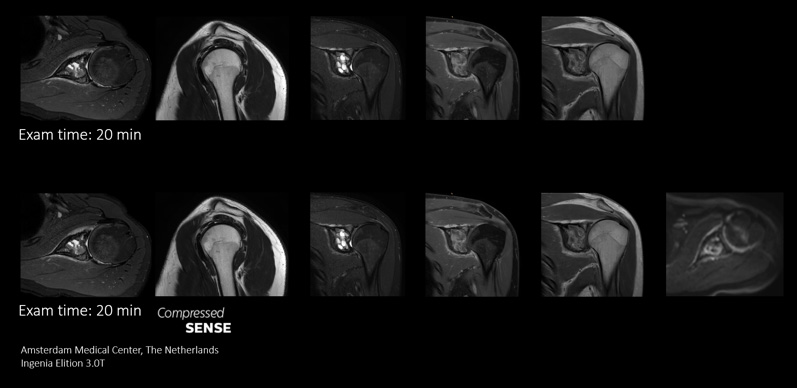

In conventional MRI scan techniques, high resolution imaging can involve long scan times which may be difficult for patients experiencing pain and discomfort. Long scan times can also make it difficult to fit high resolution imaging into acceptable MRI scan time slots for busy departments. Compressed SENSE enables fast 3D submillimeter (0.7 mm or less) isotropic images in less than 5 minutes to help diagnose challenging patients and anatomies.

Compressed SENSE gives MRI departments the flexibility to acquire as much relevant information as possible within the MRI scan time slot. Its speeds allows extra routine and functional sequences to be added to enhance diagnostic information.

This case demonstrates the ability to add additional sequences within the same time slot to enhance your diagnostic confidence. Besides traditional TSE sequences, you can now add a functional DWI sequence within the same timeslot, providing additional information for you to base your diagnosis on.